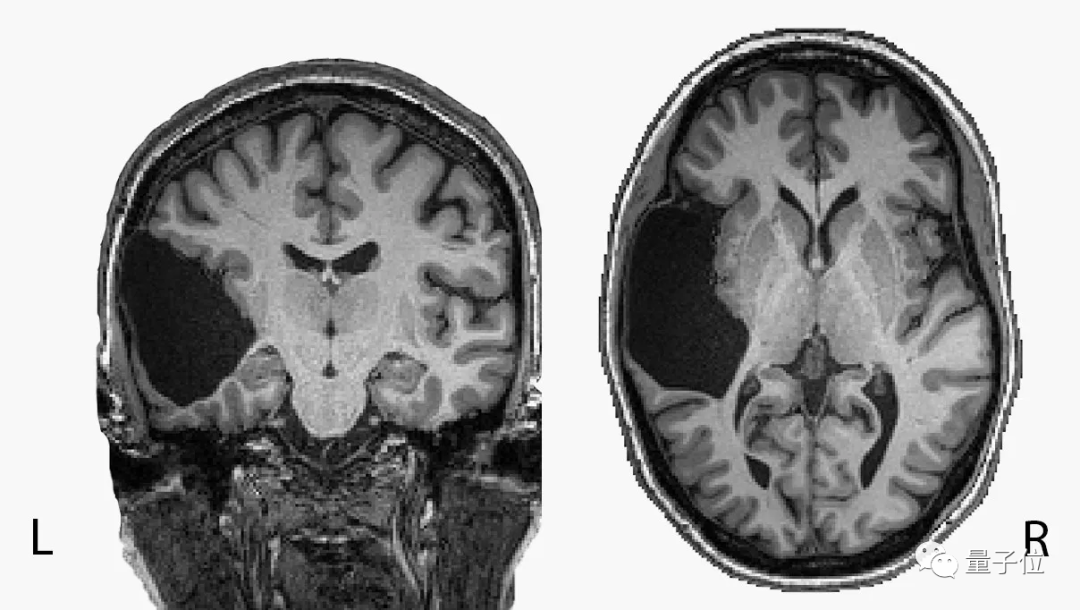

近日,一名神奇的女子登上热门,该名女子左脑缺失了一部分,奇特的是这不仅没有影响到她的日常生活,甚至还顺利的完成了她的研究生学业,并对母语英语和俄语十分精通。

这名女子(化名 EG)在自己 25 岁时发现自己的左脑缺失了一部分,不仅自己的脑干不完整,甚至原本属于左颞叶的地方也已经成为了液体,但她依旧学会了两种语言,使她的语言 IQ 测试排进前 2%。

这则趣闻告诉我们,「脑子进水」并不一定代表着它比别人更笨。甚至还有网友调侃道自己脑子挺全的,但不聪明,希望有人能研究一下这背后的原因。